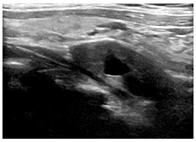

入院后行甲状腺超声示甲状腺左叶上、下极深方甲状旁腺区见2个囊实性结节,大小分别为2.9cm×1.4cm×1.1cm、2.3cm×1.4cm×1.2cm,均形态规则,边界清晰,CDFI:内见较丰富血流信号(图1,图2,图3,图4)。行甲状旁腺融合显像(显像剂:99Tcm-MIBI)示甲状腺左叶上极后上方见结节样显像剂浓聚灶,相应CT层面示椭圆形软组织密度影,边界清,大小约27.6mm×18.2mm×16.0mm。CT另见甲状腺左叶下极后下方一椭圆形软组织密度影,边界较清,大小约25mm×13.7mm×12.5mm,相应ECT层面未见显像剂摄取(图5,图6)。行嗜铬细胞瘤融合成像(显像剂:131I-MIBG)示颈部及腹部可见显像剂摄取病灶(图7,图8)。

超声图像中左侧甲状旁腺区2枚囊实性结节形态、回声、位置及血流均相似,结合实验室检查及临床病史,均提示为甲状旁腺腺瘤,但甲状旁腺融合成像仅支持甲状腺左叶上极后方结节为甲状旁腺腺瘤。甲状腺左叶下极后方结节无99Tcm-MIBI显像剂摄取,但有131I-MIBG高摄取,故综合以上考虑甲状腺左叶上极后方结节为甲状旁腺腺瘤,左叶下极后方结节为副神经节瘤。